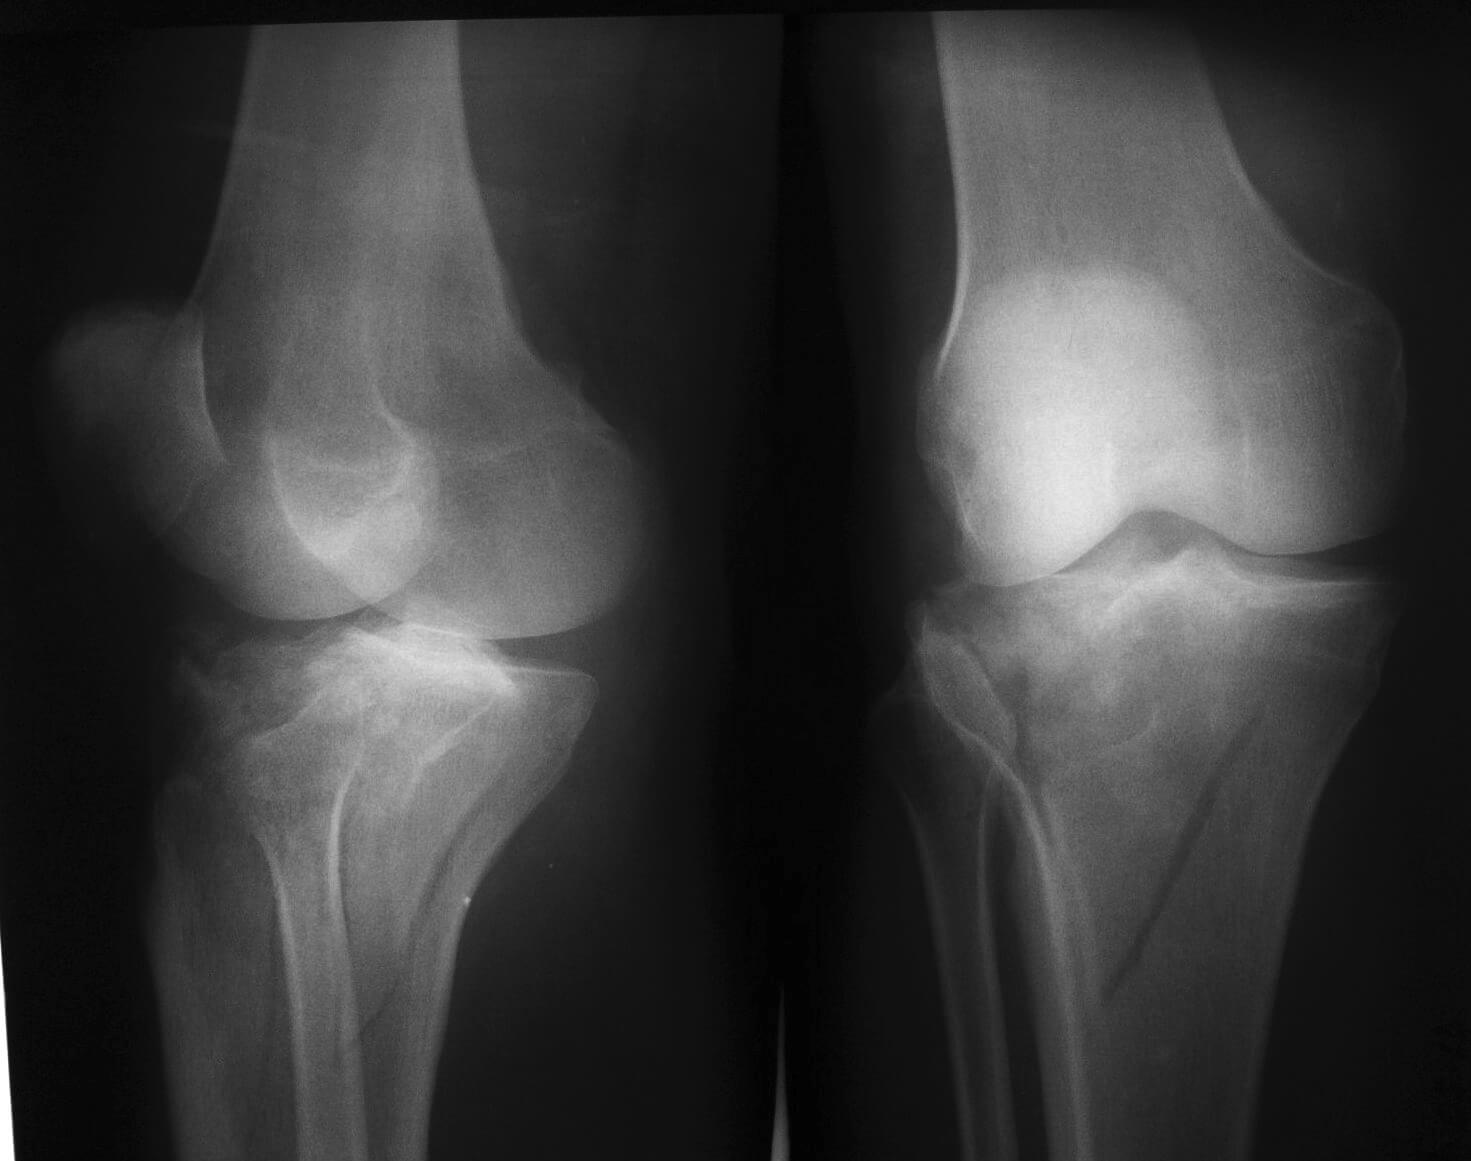

- рентген;

По результатам рентгенографии выделяют три степени повреждений. Основаны они на определении отклонении угла, под которым находится коленное сочленение:

- 1 степень — изменение угла не более трети от исходного.

- 2 степень — изменение уже более трети или наполовину, но целостности менисков на 2 ст. сохранена.

- 3 степень- угол нарушен полностью, наблюдаются осколки.